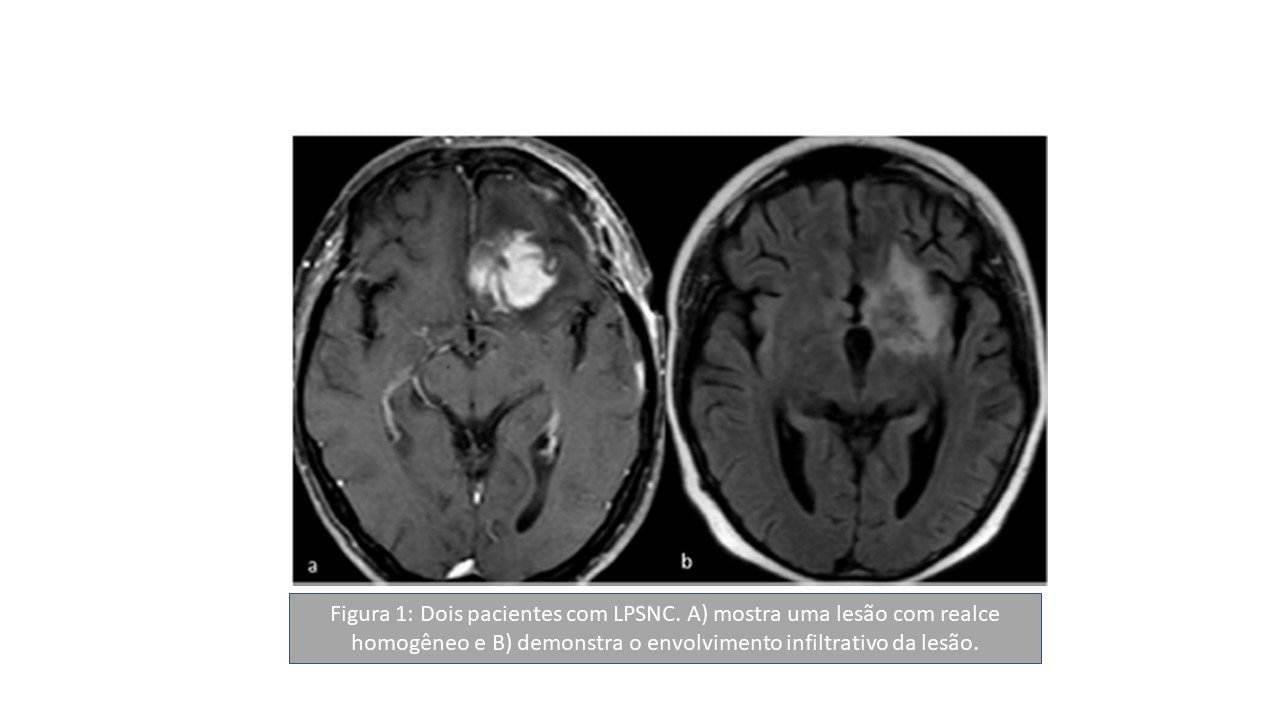

Padrões de imagem na ressonância magnética de linfomas do sistema nervoso central: uma revisão pictórica